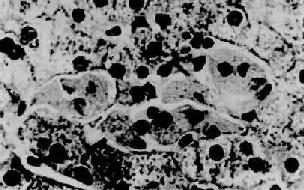

图10-33 高雪病之肝 图中央区为数个高雪细胞,位于肝窦内胞浆呈皱纹纸状外观 2.磷脂沉积症 主要为不含甘油成分的神经磷脂的增多、蓄积,又称尼曼-皮克病。 尼曼-皮克(Niemann-Pick)病又称神经磷脂沉积症。系由于常染色体隐性遗传所致的神经磷脂酶缺乏,使神经磷脂不能被水解而沉积于组织内所致。另外还可伴有其它脂质贮积。本病主要累及肝、脾、骨髓及淋巴结等器官,在儿童也侵犯神经系统。肝病变肉眼观,肝肿大。镜下,在肝窦内和汇管区有大量Kupffer细胞和巨噬细胞聚集,细胞体积肿大,胞浆呈泡沫状,核小居中,称为Pick细胞。肝细胞内也可见有脂肪,主要为中性脂肪及胆固醇。电镜下见Pick细胞内充满多数年轮样层状排列的球形包涵体。本病常发生于幼儿,预后不佳。 (四)铜代谢障碍疾病—肝豆状核变性 肝豆状核变性(hepatolenticular degeneration)又称威尔逊病(Wilson’s disease)。本病为位于第13染色体的隐性基因传递的遗传性疾病,家族性多发。患者多为儿童及青少年。本病的特点是铜代谢障碍,不能正常排出而蓄积于各器官。首先累及肝,待肝饱和后再沉积于中枢神经系统,故出现神经症状。铜也可蓄积于角膜,在角膜周围出现绿褐色环(Kayser-Fleischer环)。肝病变:在肝细胞中可见有脂褐素、铜结合蛋白、铁等沉着。铜或铜结合蛋白(如rhodamine,rubeanic acid等)可由组织化学染色检出。早期见肝细胞线粒体基质中有大颗粒或晶体沉着。肝并有急、慢性肝炎及肝硬变等病变伴发。中枢神经系统可见被壳及苍白球变性,尾状核萎缩,大脑皮质及小脑变性等。